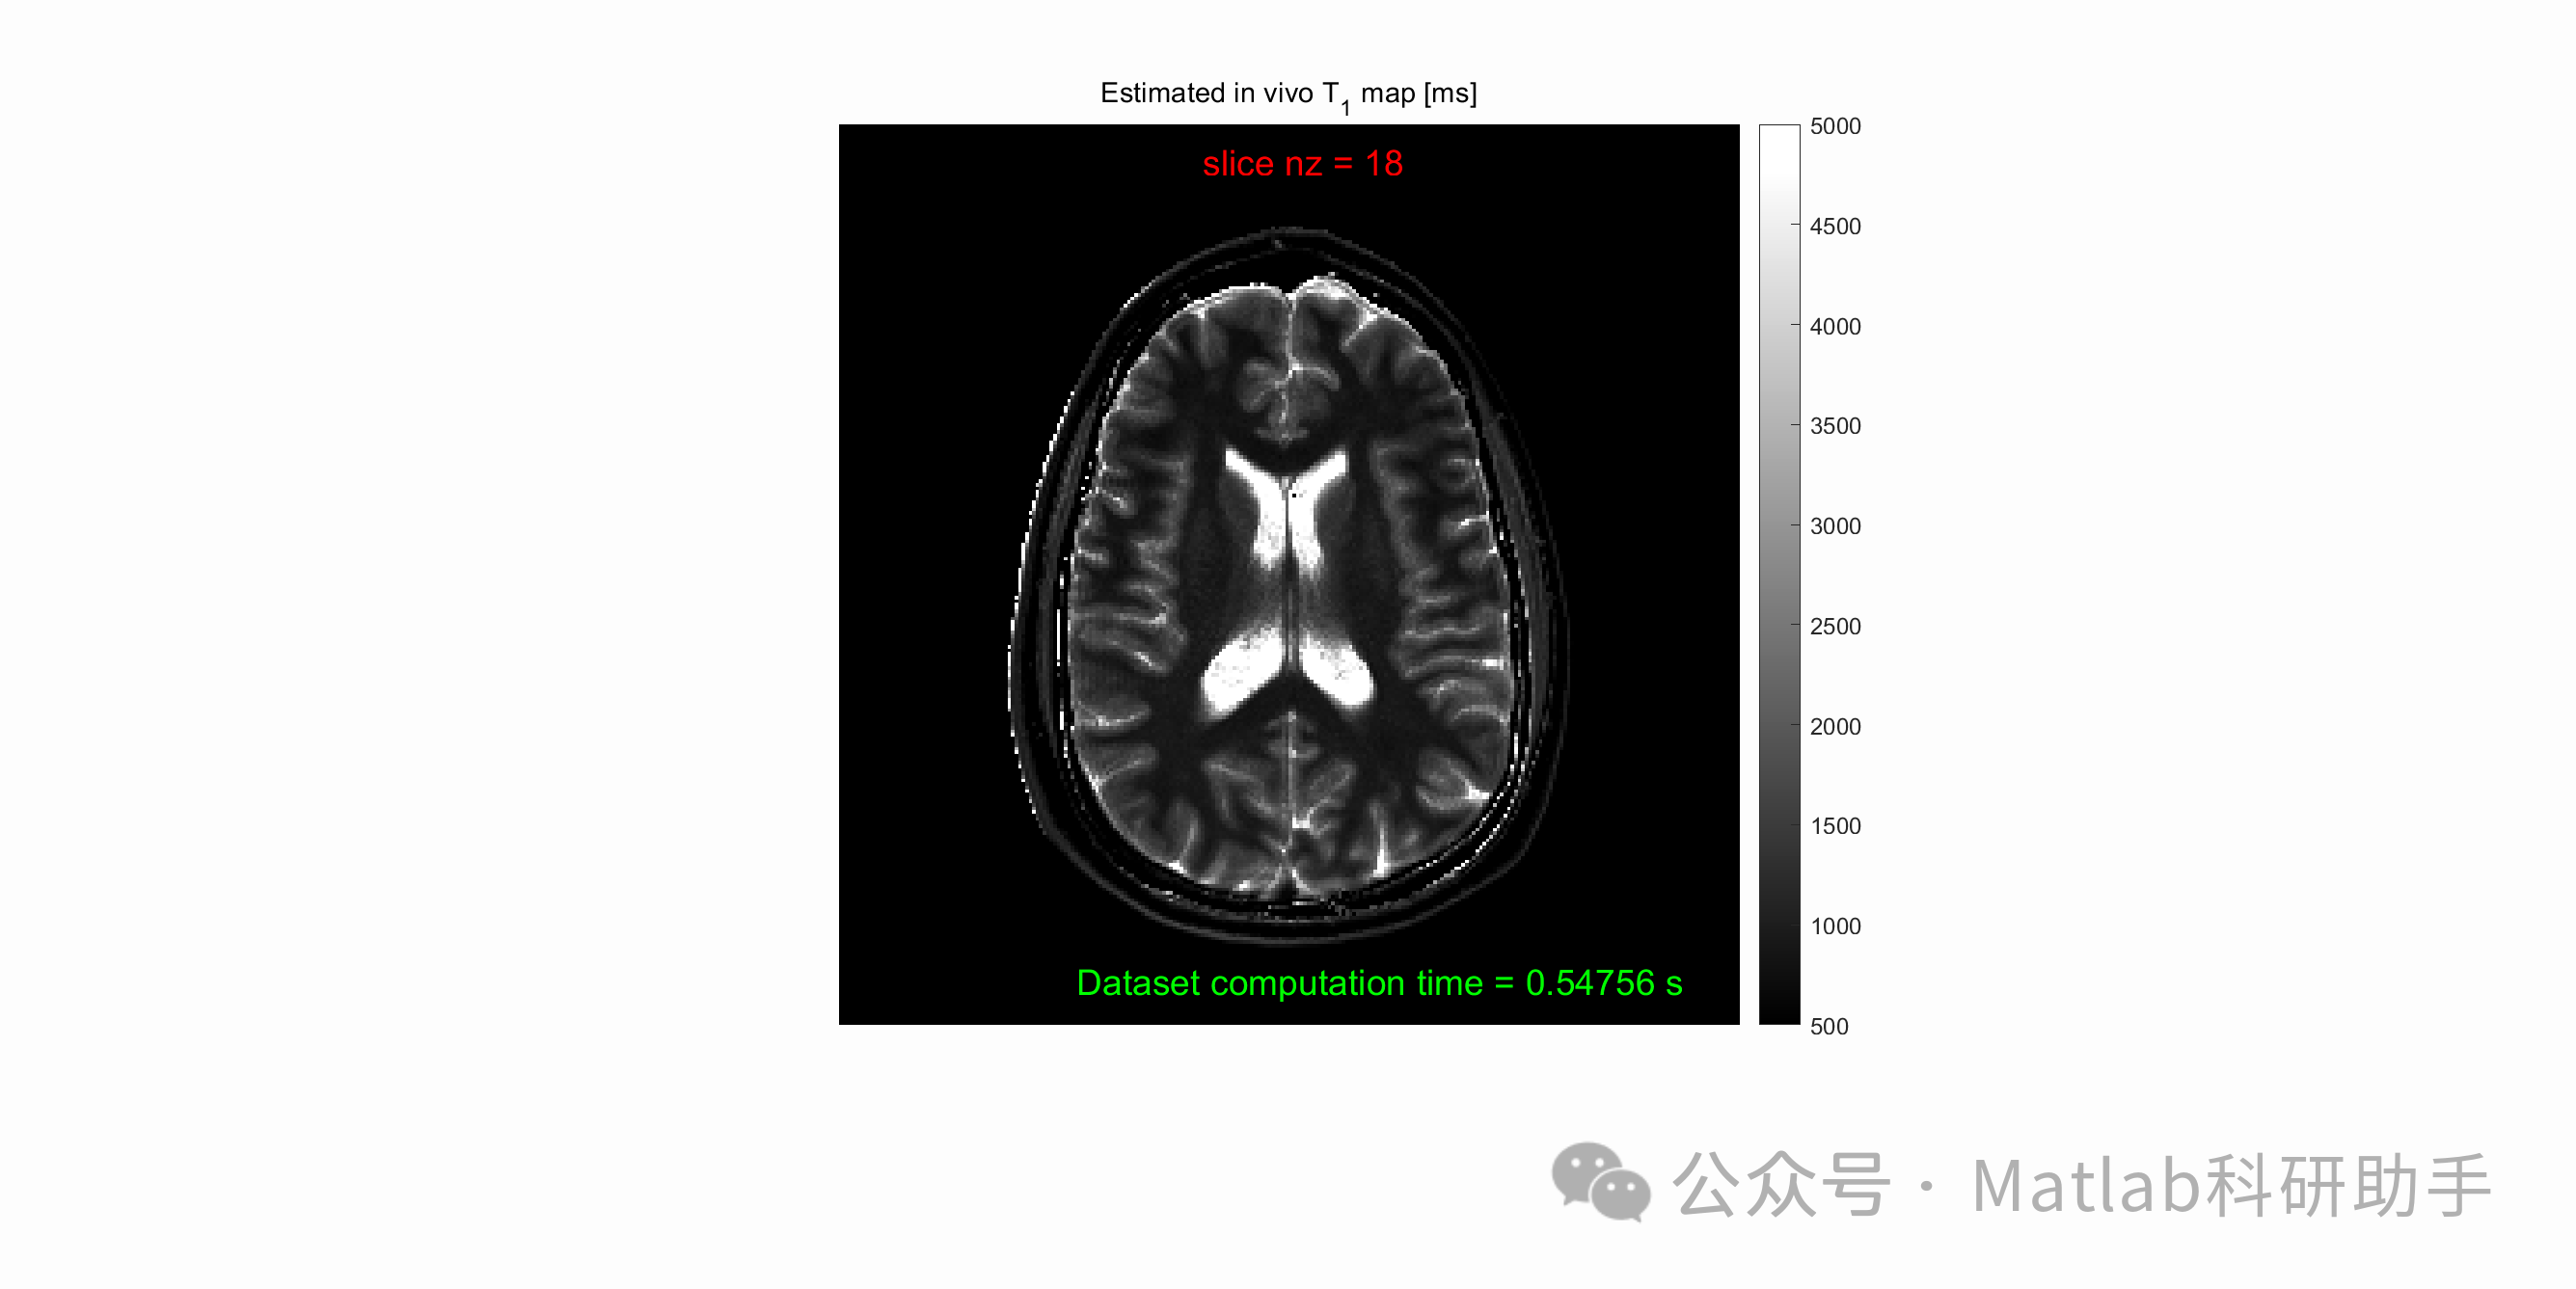

- 临床实验:

在人体受试者上进行实验。利用SPGR序列采集不同翻转角的MRI图像,并使用新型NLLS算法和传统算法进行T1映射。通过比较两种算法得到的T1映射图像的质量、T1值的分布以及诊断价值,评估算法的临床应用潜力。

⛳️ 运行结果